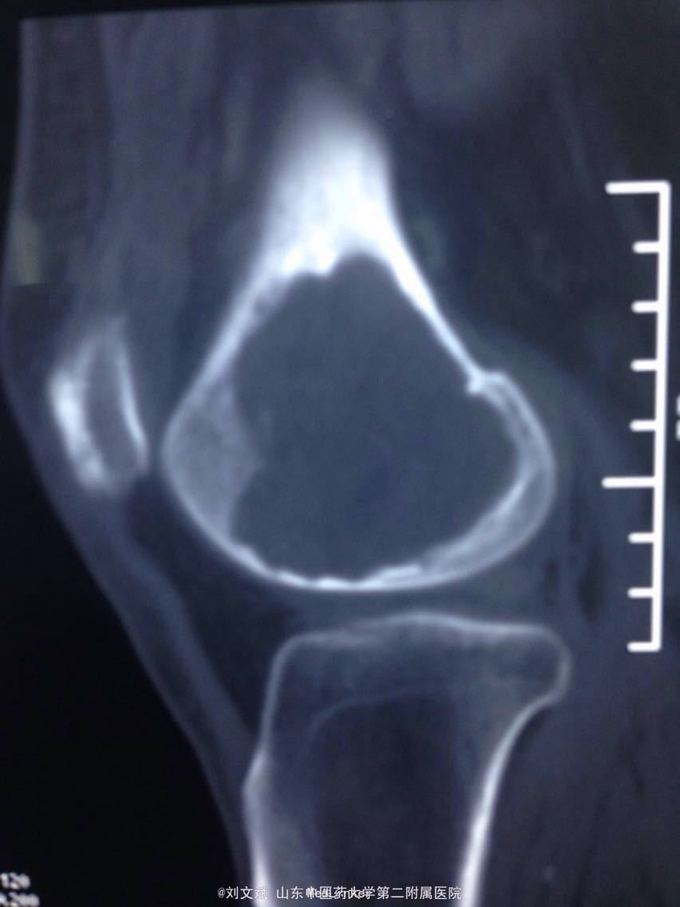

男性51岁,左膝关节疼痛不适10余年。因症状较轻,不影响活动,未曾系统诊治。一月前因扭伤致疼痛加重,拍片检查,见股骨远端骨质异常,进一步行CT示股骨髁占位病变,考虑骨囊肿。既往有高血压,糖尿病病史。近期无低热,体重下降。

诊断:左股骨远端占位 因皮质完整,行手术开窗刮除,自体髂骨及同种异体骨混合植骨填充治疗。切取组织送病理检查

刮除占位组织如图所示,送病理检查了,结果还没回来。 没有全身症状,像是原发灶,骨皮质完整,没有明显骨膜反应请专家们看看,什么可能性比较大? 补上病理结果和术后片子